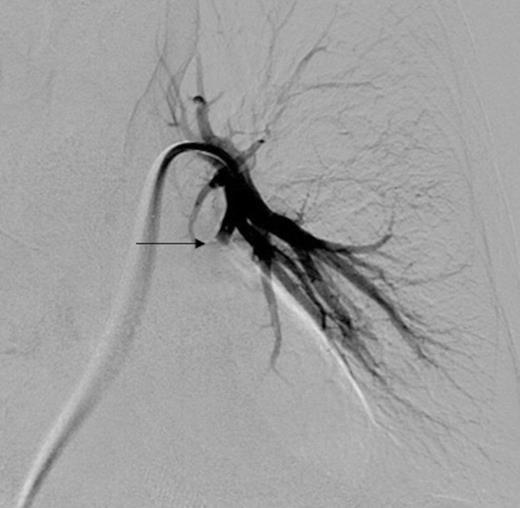

Selective digital subtraction angiography image of left lower lobe pulmonary artery, demonstrating filling of the inflammatory aneurysm and depicting the feeding branches clearly

Digital subtraction angiography post deployment of the AVP 4 device in the PA branch feeding the aneurysm (arrow). No residual or collateral filling seen